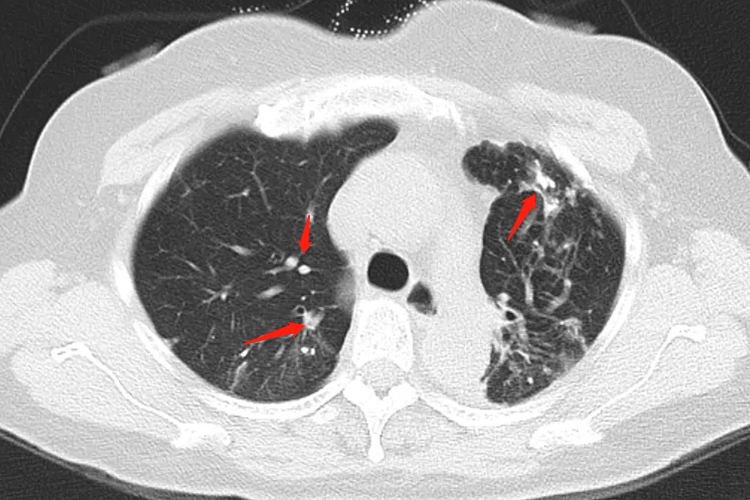

- 干酪样坏死的诊断通常结合患者的临床表现、影像学检查和实验室检查结果进行综合分析。影像学检查如肺部X线片和CT扫描可显示肺部病变的范围和程度,而痰培养可检出结核分枝杆菌,是确诊肺结核的重要手段之一。